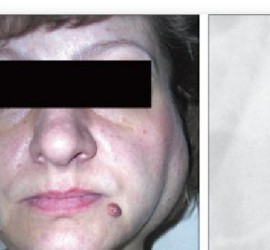

Франкфуртская горизонталь — немецкая горизонталь, введена как антропологическая измерительная плоскость на антропологическом конгрессе во Франкфурте-на-Майне в 1884 г., проходит через верхний край наружного слухового прохода и самую глубокую точку глазницы. В клинике ориентирами являются: верхний край козелка уха и пальпаторно — нижний край орбиты.